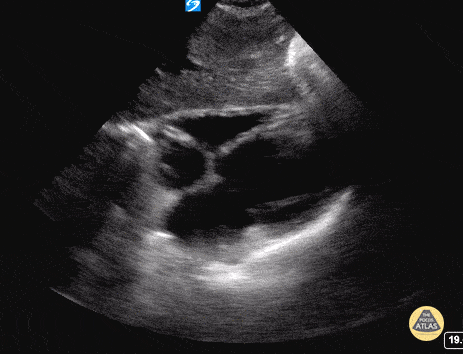

Normal Cardiac Anatomy - Subxiphoid / Subcostal - Normal

The most superficial structure we see is the liver. Immediately deep to that we see the heart separated from the liver by the diaphragm. Closest to the liver is the right atrium, tricuspid valve, right ventricle. Deeper to that, we see the left atrium, mitral valve, and left ventricle. Hannah Kopinski - MS4, Dr. Lindsay Davis - NYU/Bellevue Department of Emergency Ultrasound, Dr. Matthew Riscinti - Kings County Emergency Medicine